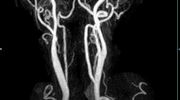

MR-Angiografie (MRA)

• MR-Angiografie ohne Kontrastmittel

• Time of Flight (TOF)-Angiographie

Je nach Fragestellung und Körperregion Gefäßdarstellung ohne Kontrastmittel bei Kontrastmittelunverträglichkeit oder terminaler Niereninsuffizienz möglich.

• MR-Angiographie mit Kontrastmittel

• Erfassung arterieller und venöser Gefäße/Bypässe aller Körperregionen mit 3D-Rekonstruktion